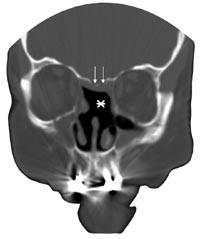

Pasient 2. En 58 år gammel kvinne ble operert for tredje gang med transseptal, transsfenoidal tilgang for residiv av kromofobt hypofyseadenom. Pasienten hadde økende synsfeltsutfall, og adenomet vokste infiltrerende i skallebasis med gjennomvekst til sinus sphenoidalis. Etter inngrepet oppstod rhinoré, og CT caput viste pneumatocephalus. To endoskopiske operasjoner med transnasal tilgang ble gjennomført for å lukke lekkasjen, men begge var mislykte. CT-bilde viste en stor beindefekt i den fremre veggen og i gulvet av sella turcica (fig 2). Nesesekretet inneholdt 8,2 mg/l betasporprotein. Tredje forsøk på å lukke lekkasjen ble gjennomført med natriumfluoresceinfarging (fig 3). Defektene ble dekket med autolog fascia lata. På grunn av hydrocephalus ble det lagt en ventrikuloperitoneal shunt. Den postoperative CT-undersøkelsen viste ikke intrakranial luft, og ved kontroll etter fem måneder hadde hun ikke tegn til likvoré.